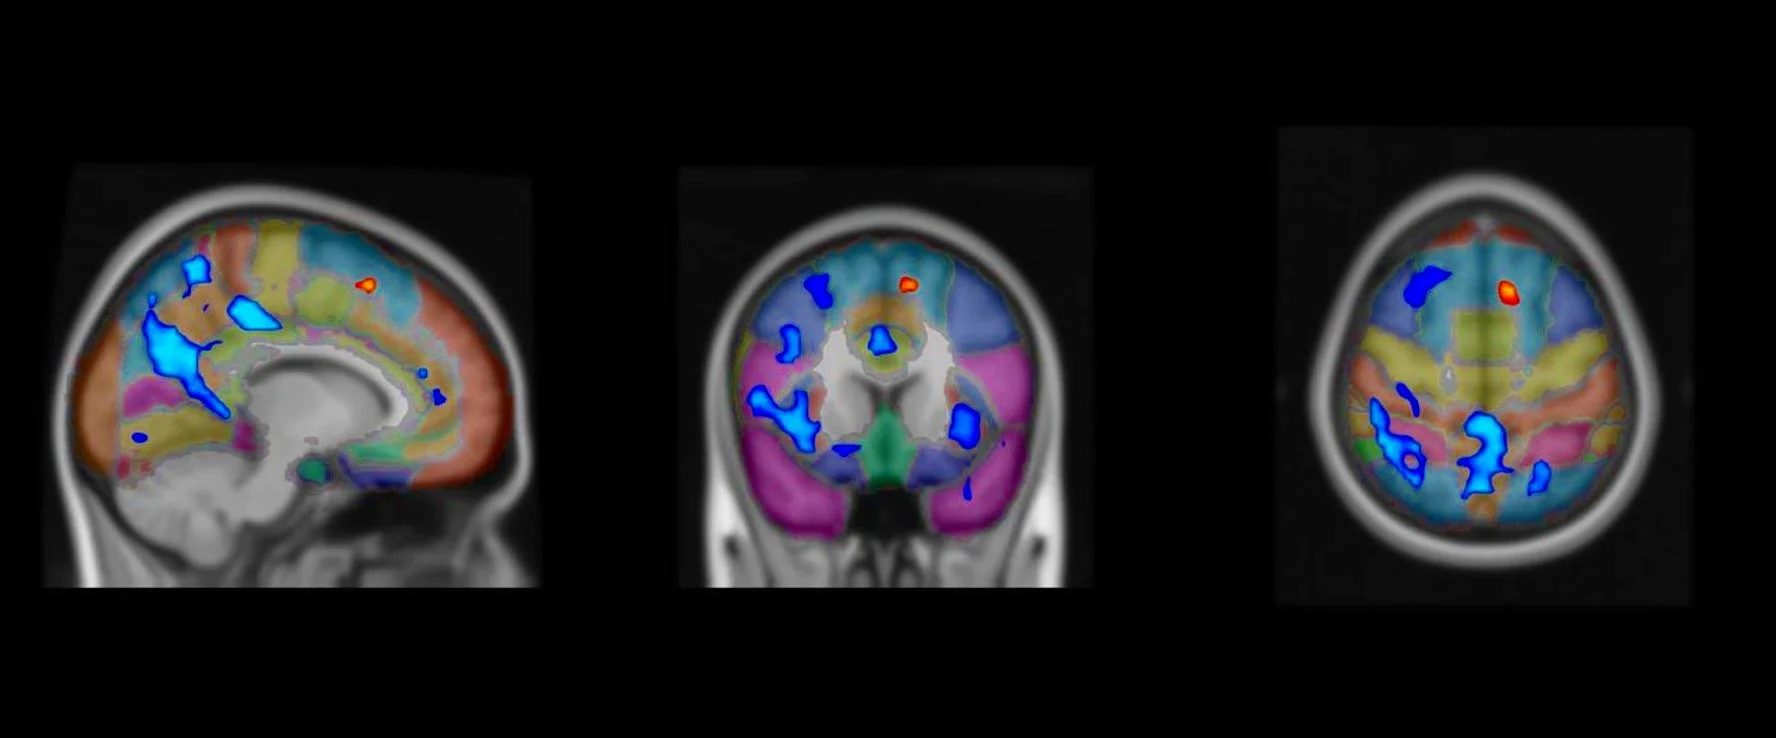

Utilizing cutting-edge neuroscientific and phenomenological techniques developed in the study of meditation and consciousness, we delve into the less-charted domain of Christian prayer. We have preliminary significant findings showing that speaking in tongues involves letting go (preSMA deactivation) and cognitive loosening (Increased divergent thinking). Our goal is to explore the potential of prayer for enhancing compassion, relaxation, fostering self-transcendence and boosting cognitive flexibility, and shaping the balance between universalist and parochial experience of compassion and community.